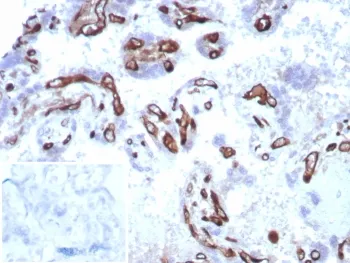

FABP4 Recombinant Antibody

Fatty acid-binding proteins, designated FABPs, are a family of homologous, cytoplasmic proteins that are expressed in a highly tissue-specific manner and play an integral role in the balance between lipid and carbohydrate metabolism. FABPs mediate fatty acid (FA) and/or hydrophobic ligand uptake, transport and targeting within their respective tissues. The mechanisms underlying these actions can give rise to both passive diffusional uptake and protein-mediated transmembrane transport of FAs. FABPs are expressed in adipocytes (A-FABP), brain (B-FABP), epidermis (E-FABP, also designated psoriasis-associated FABP or PA-FABP), muscle and heart (H-FABP, also designated mammary-derived growth inhibitor or MDGI), intestine (I-FABP), liver (L-FABP), myelin (M-FABP) and testis (T-FABP). The human A-FABP gene is organized into 4 exons, maps to chromosome 8q21.13, and encodes a 132 amino acid protein. A-FABP protein comprises approximately 1% of the total cytosolic protein in human adipose tissue.UniProt:

RabbitImmunogen:

A recombinant partial protein sequence (within amino acids 1-132) from the human protein was used as the immunogen for the Fatty Acid Binding Protein 4 antibody.Clonality:

RecombinantApplications:

IHC-PFormat: